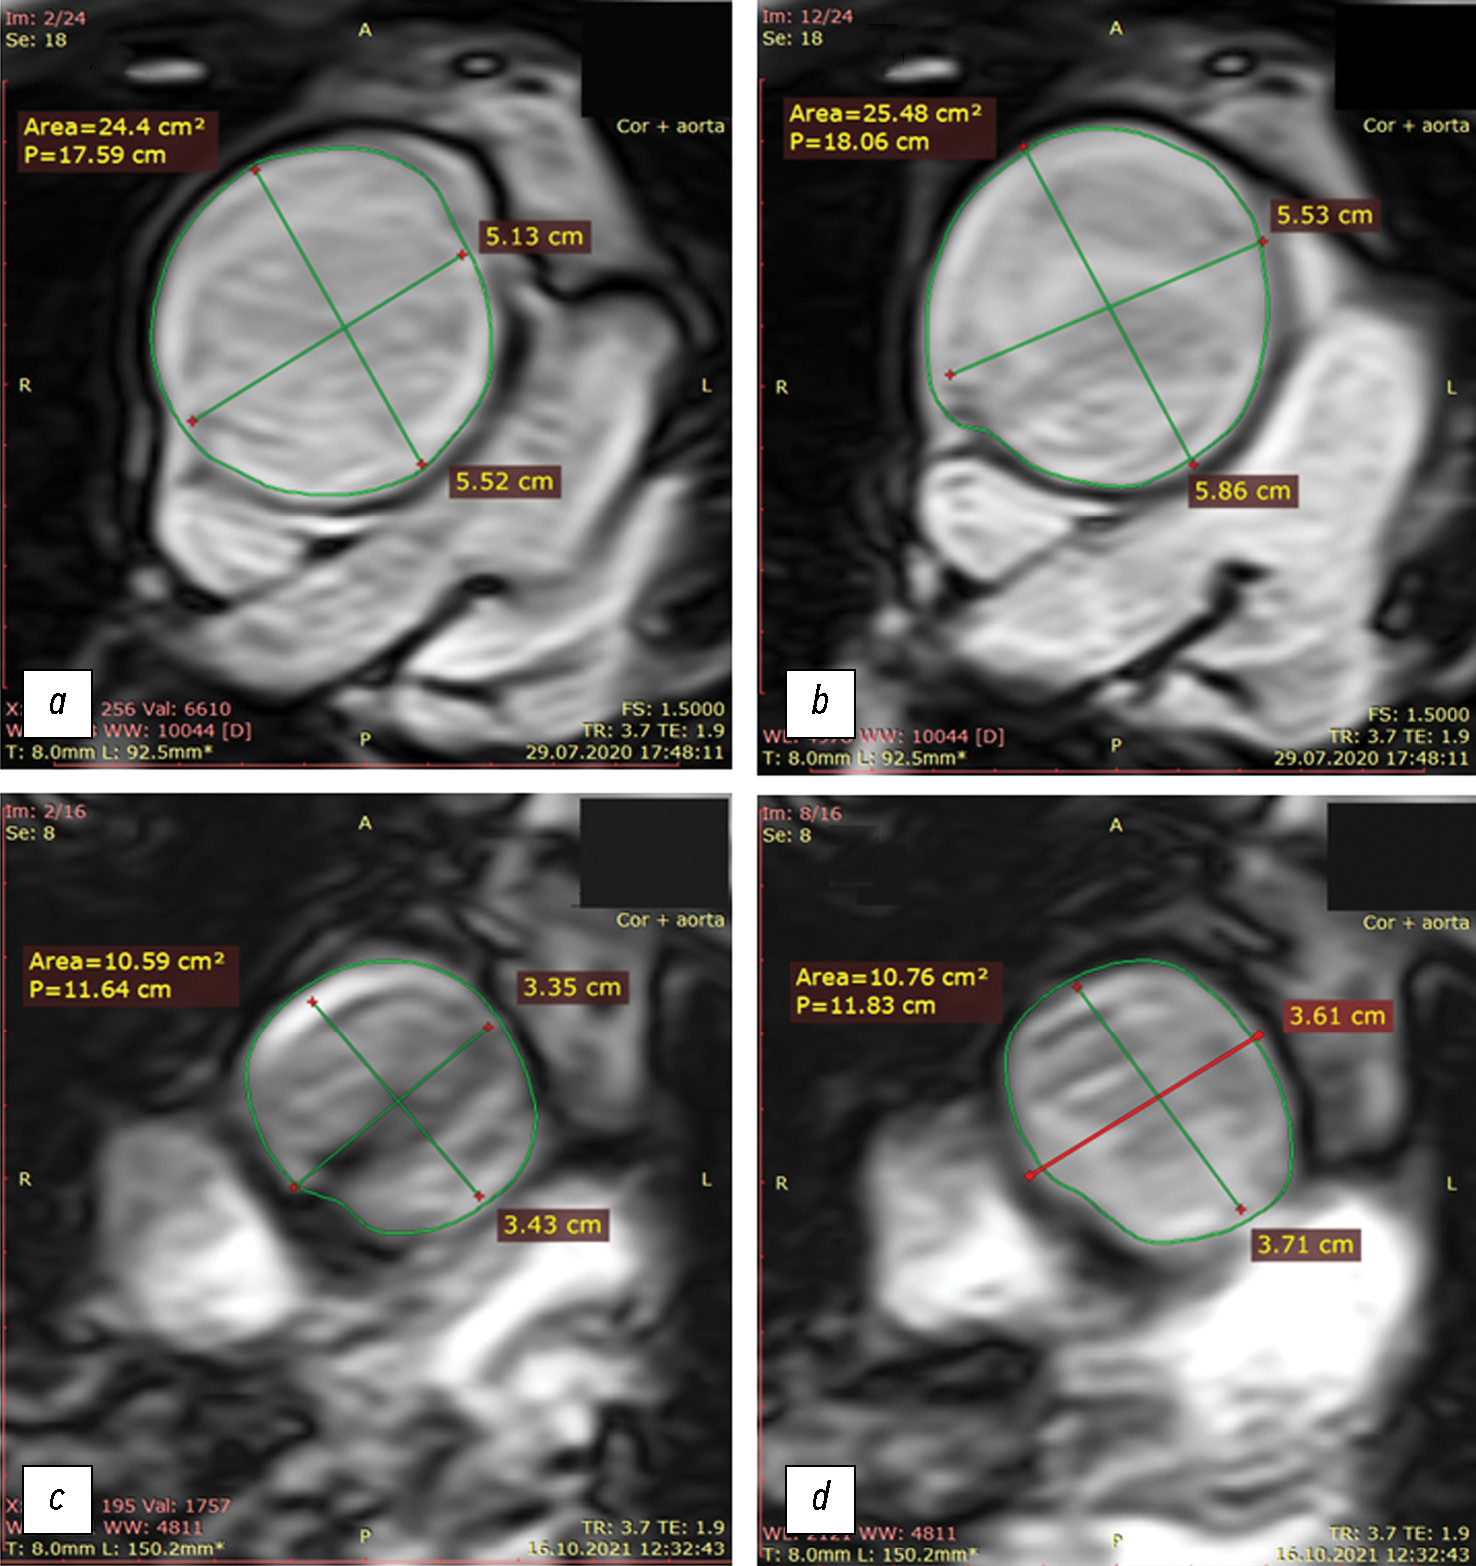

Fig. 3. Cross-sectional dimensions and areas of the ascending aorta during systole and diastole: top row: baseline (at admission; before replacement of the aorta that expanded due to aneurysm); bottom row: after replacement with a synthetic graft; (a, c) diastole; (b, d) systole. Of note is a considerable lumen narrowing after surgery, with a relatively small distensibility of the ascending aorta.